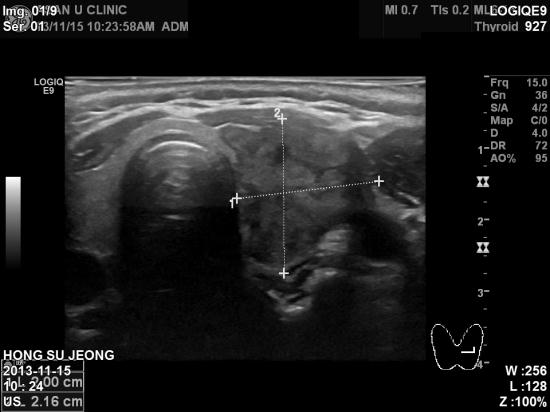

아산유외과 개원 후 11번째 갑상선암 진단.

건강검진에서 갑상선 초음파상 이상소견이 있어

본원으로 의뢰되신

50

세

여자분이십니다

.

좌측 갑상선에

2cm

가 넘는 혹이 있어

세포검사 시행결과 유두암으로 진단되셨습니다

갑상선 유두암은 갑상선암중 가장 흔하며 예후도

가장 좋습니다